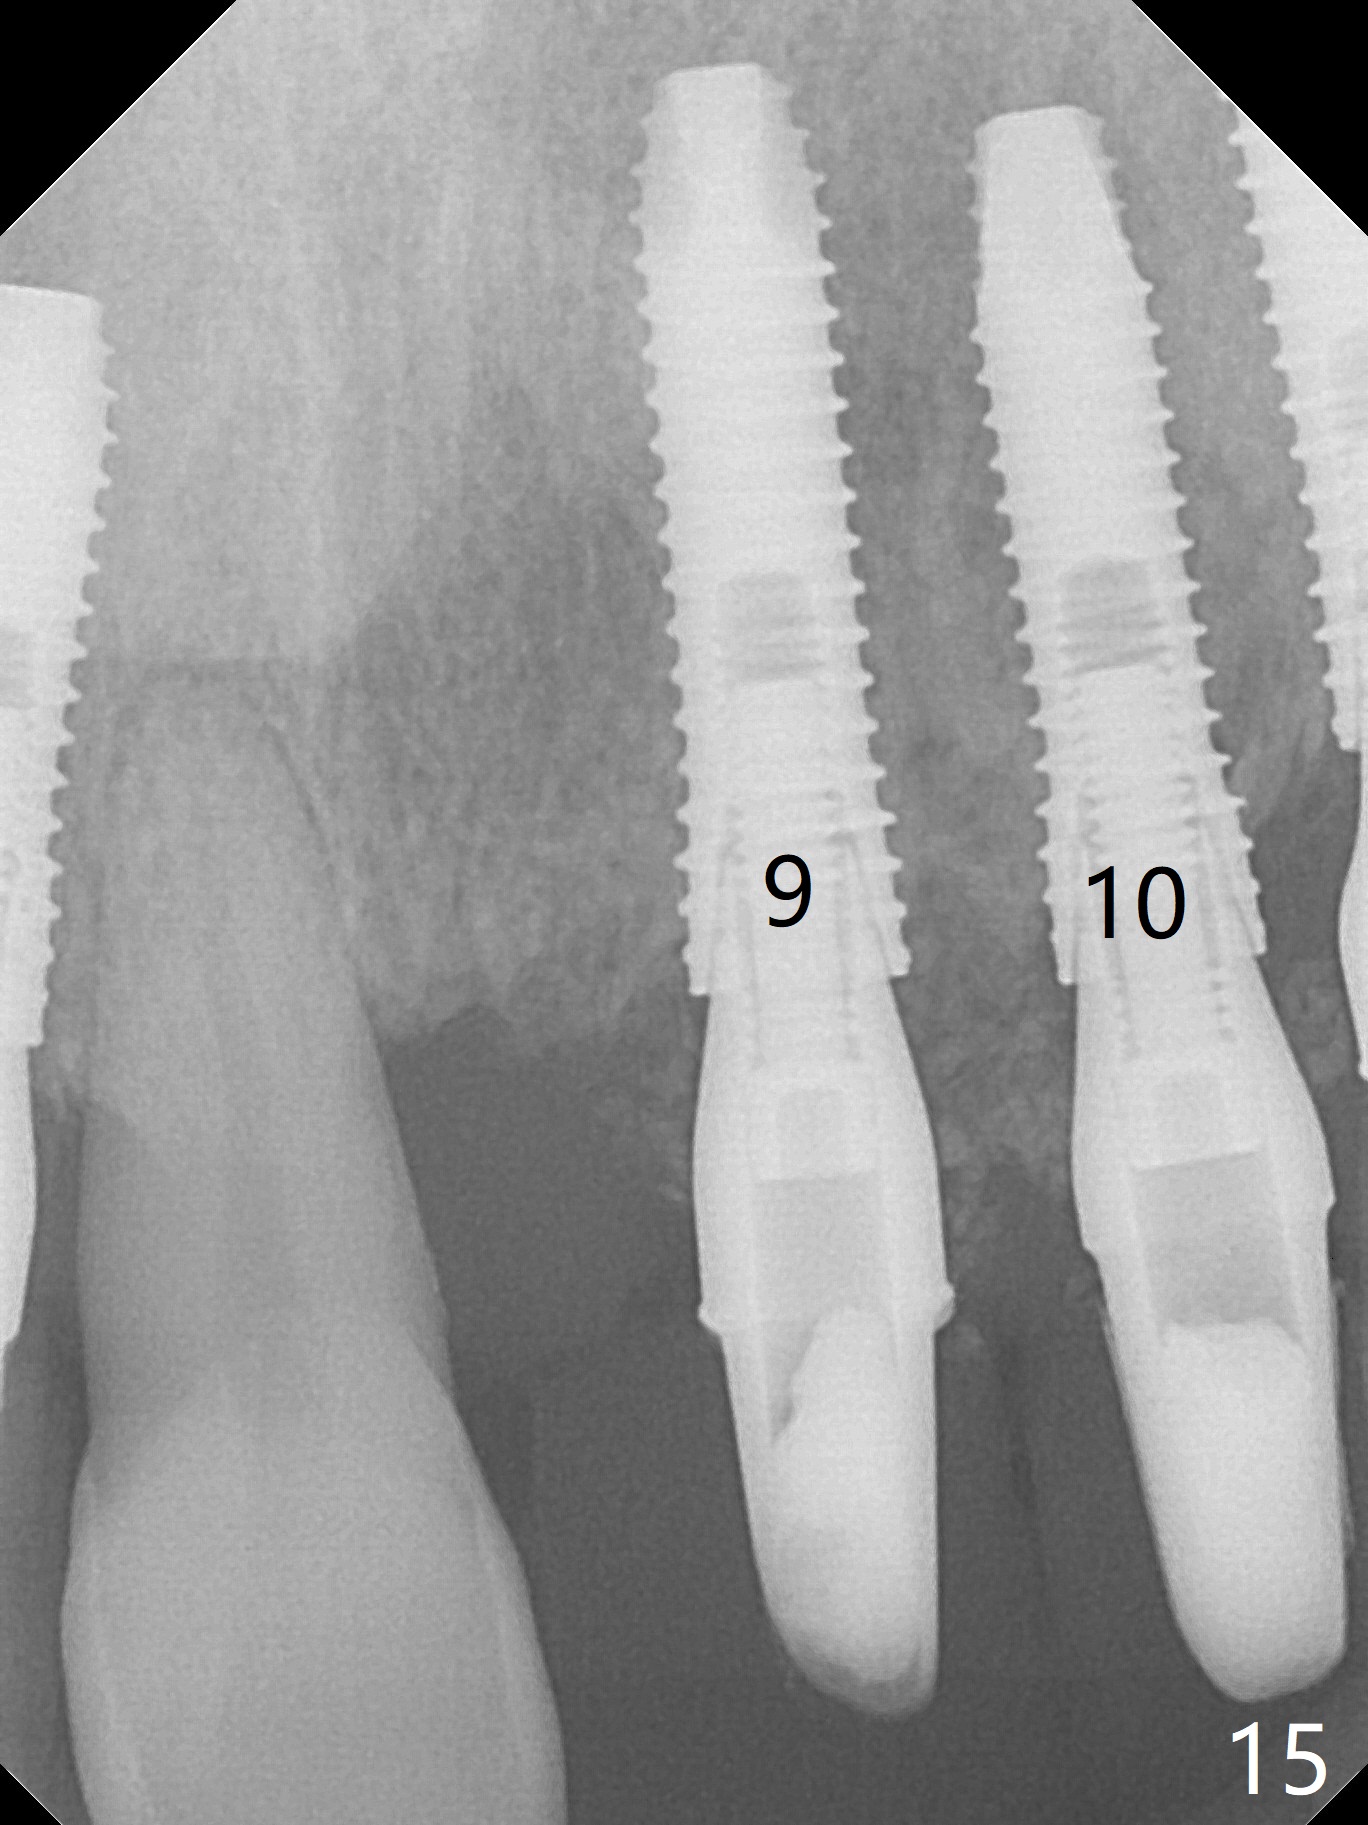

After use of 3 mm drill, the implant is reinserted at #11 with ideal trajectory (Fig.7). After further seating of the implant at #11, graft is placed in the remaining sockets of #9-11 (Fig.8 *; later more graft is placed mesial to #11 implant (^)). There appears no thread exposure 7 months postop (Fig.15,16).